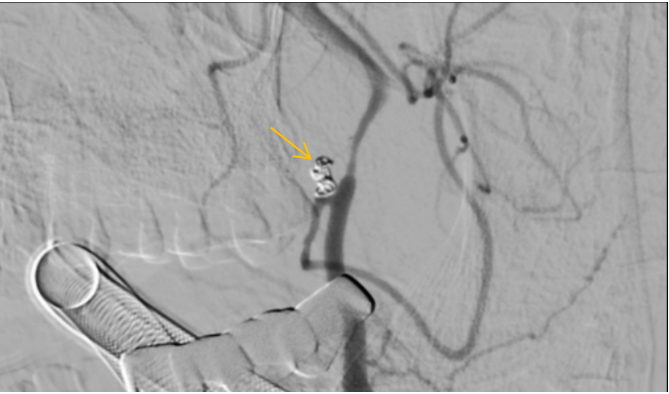

神经外科二区主任李成林及团队详细评估病情,发现该动脉瘤位于小脑后下动脉的起始部,且瘤颈宽,意味着手术难度比一般动脉瘤更高,“拆弹”难度巨大。神经外科二区专家团队手术经验丰富,立即根据患者病情制订了手术方案,经家属同意后,立刻实施栓塞动脉瘤的手术,最终成功为李女士拆除大脑的“定时炸弹”。

位于后循环的右侧小脑后下动脉瘤被成功栓塞